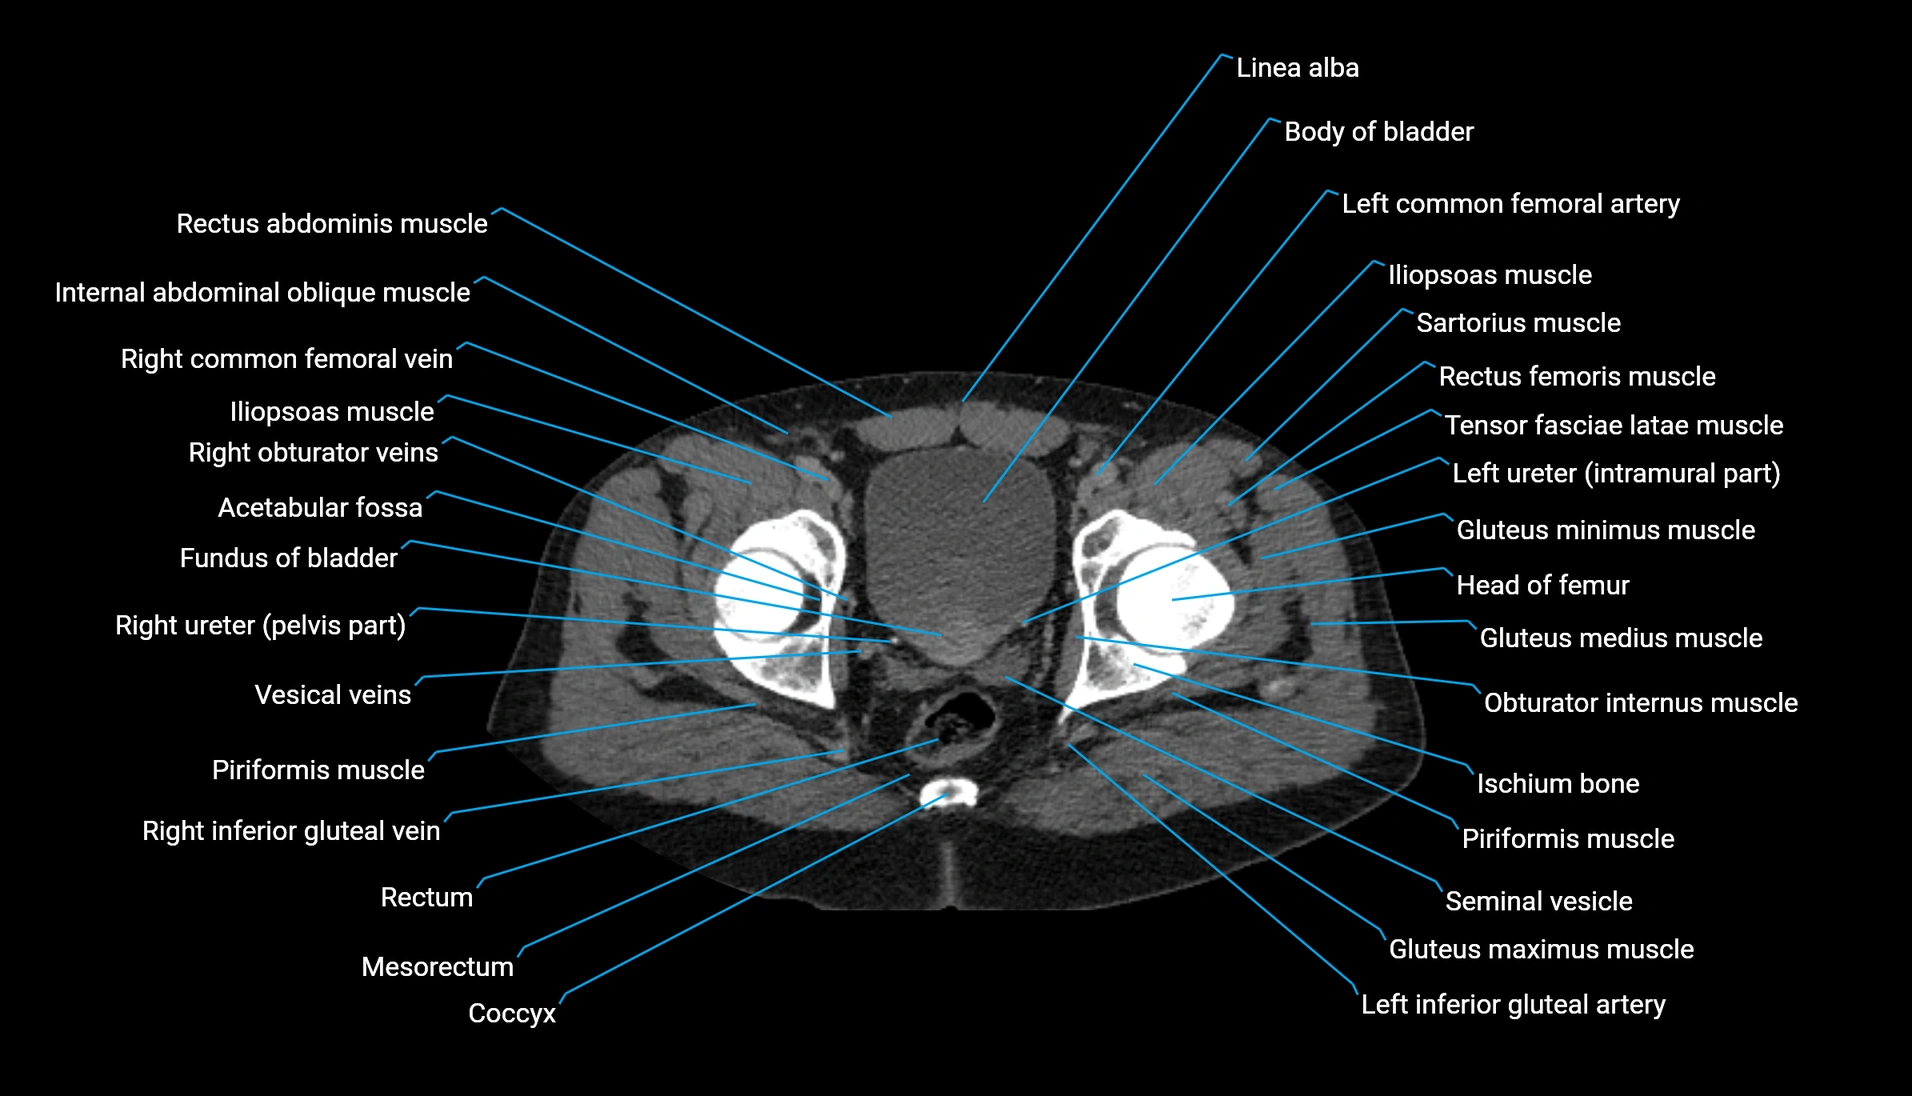

CT Appearance

Non-contrast CT:

-

Demonstrates cortical bone of acetabular rim in excellent detail

Detects fractures, dysplasia, retroversion, or bony overcoverage (pincer impingement)

3D reconstructions used in preoperative hip surgery planning

CT image